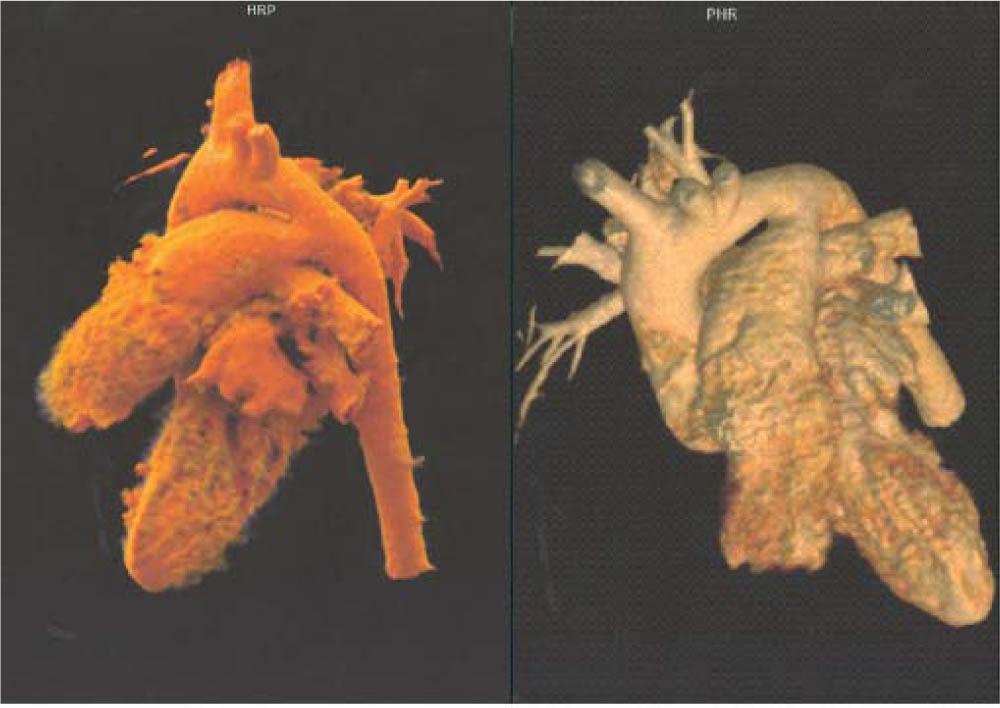

Figure 2